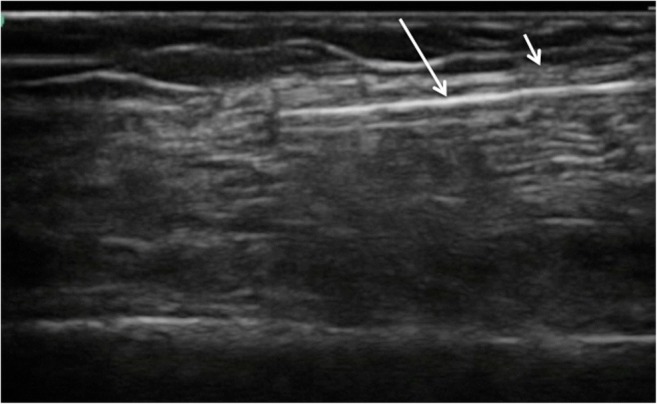

Fig. 2.

Real-time ultrasound image of blunt tunneling (long white arrow) device passing immediately deep to fascial plain (short white arrow)